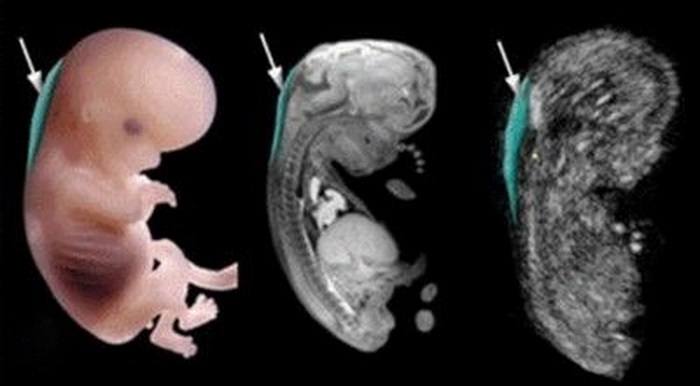

Ультразвуковое исследование, проведенное во второй половине беременности, отображает кисту ассиметричной формы в шейном отделе с тонкими стенками и перегородками. На фотографии внешний вид лимфангиомы представлен темным пятном с нечеткими границами.Большое значение при проведении ультразвукового исследования имеет его точность и чистота измерения, поскольку велика вероятность ошибок и постановок ложного диагноза при неверном проведении.

Ультразвуковое исследование, проведенное во второй половине беременности, отображает кисту ассиметричной формы в шейном отделе с тонкими стенками и перегородками. На фотографии внешний вид лимфангиомы представлен темным пятном с нечеткими границами. Большое значение при проведении ультразвукового исследования имеет его точность и чистота измерения, поскольку велика вероятность ошибок и постановок ложного диагноза при неверном проведении.